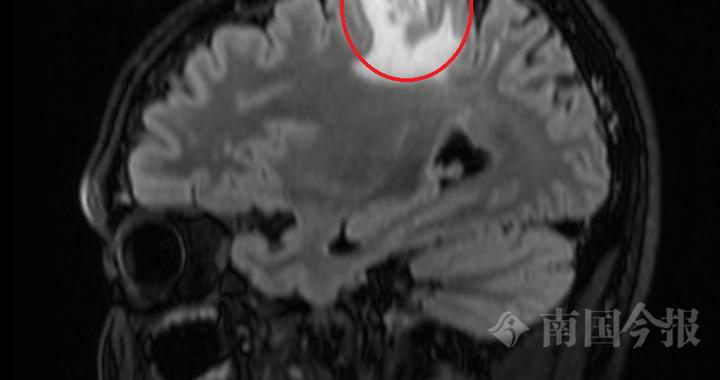

脑袋里“挖”出8厘米活虫!这个“土方子”害人不浅,很多人还在用! 最终医生在影像中发现关键线索:病灶会“移动”,还留下了“隧道”痕迹——这是虫子在脑里爬行的罪证。开颅手术后医生成功捕获一条8厘米长的活虫:裂头蚴被称为会“打隧道”的寄生虫图源:百度百科图中长得很像金针菇的虫子就是裂头蚴是曼氏迭宫绦虫的幼虫阶段裂头蚴是怎样生存的... 2026-05-12 13:22:00